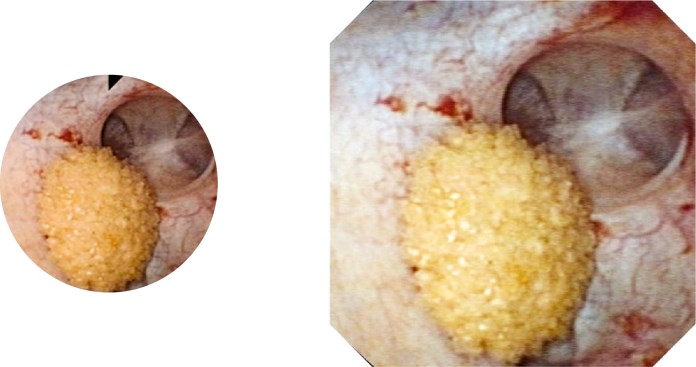

Морфология: Узкоспектральная эндоскопия

NBI помогает при наблюдении за морфологией слизистой оболочки; принцип работы NBI заключается в изменении источника белого света в сторону определенных диапазонов длин волн, которые помогают воспользоваться преимуществами характеристик тканей человека в плане рассеивания и поглощения. Это обеспечивает лучший визуальный контраст поверхностной стриктуры и тонких капиллярных рисунков слизистой оболочки, которые сложно различить в обычных условиях. NBI использует преимущества света, проникающего сквозь слизистую оболочку посредством более четкого отображения капилляров в поверхностном слое слизистой оболочки, чем при использовании традиционного белого света.